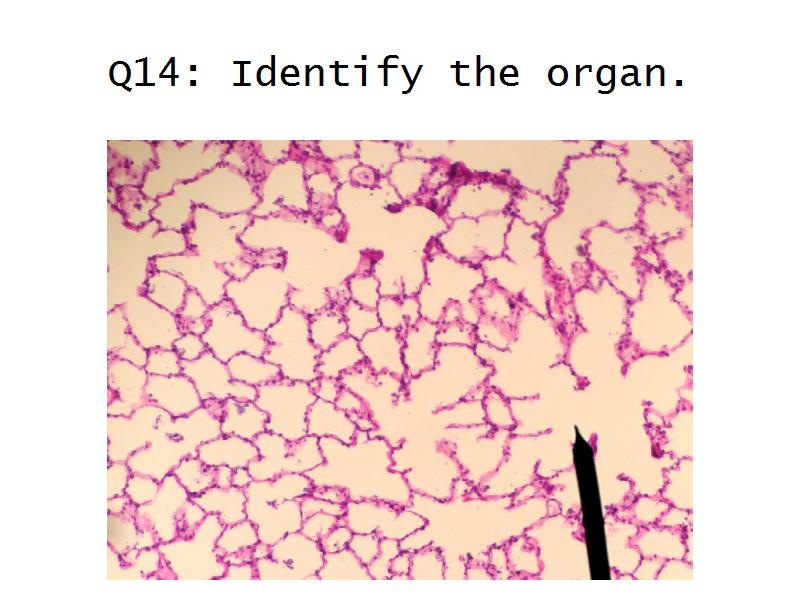

- The renal corpuscle